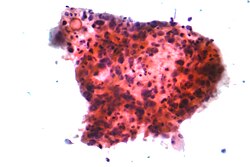

Karcinomi pluća se klasificiraju prema histološkom tipu.[8] Ova klasifikacija je važna za određivanje liječenja i prognozu ishoda bolesti. Većina zloćudnih tumora pluća su karcinomi, zloćudni tumori koji potječu od epitelnih stanica. Karcinomi pluća se svrstavaju na osnovi izgleda zloćudnih stanica koje određuje patolog, pomoću mikroskopa. Dvije najšire skupine su ne-sitnostanični i sitnostanični karcinomi pluća.[44]

Oko 40% karcinoma pluća su adenokarcinomi, koji se obično počinju razvijati na periferiji pluća.[8] Većina adenokarcinoma je povezana s pušenjem, međutim u osoba koje su u životu popušile manje od 100 cigareta (što se računa kao da nisu nikada pušile),[1] adenokarcinom je najčešći oblik karcinoma pluća.[45] Podtip adenokarcinoma, bronhioloalveolarni karcinom, je učestaliji u žena koje nikada nisu pušile i može imati bolju dugoročnu prognozu.[46]

Karcinom pločastih stanica (planocelularni karcinom) čini oko 30% svih karcinoma pluća. On se tipično razvija u velikim bronhima. U središtu ovog tumora često se nalazi šupljina uslijed nekroze tumorskih stanica.[8]Oko 9% karcinoma pluća su velikostanični karcinomi, koji se nazivaju tako jer su tumorske stanice izrazito velike, s obilnom citoplazmom, velikim jezgrama i uočljivim nukleolima.[8]